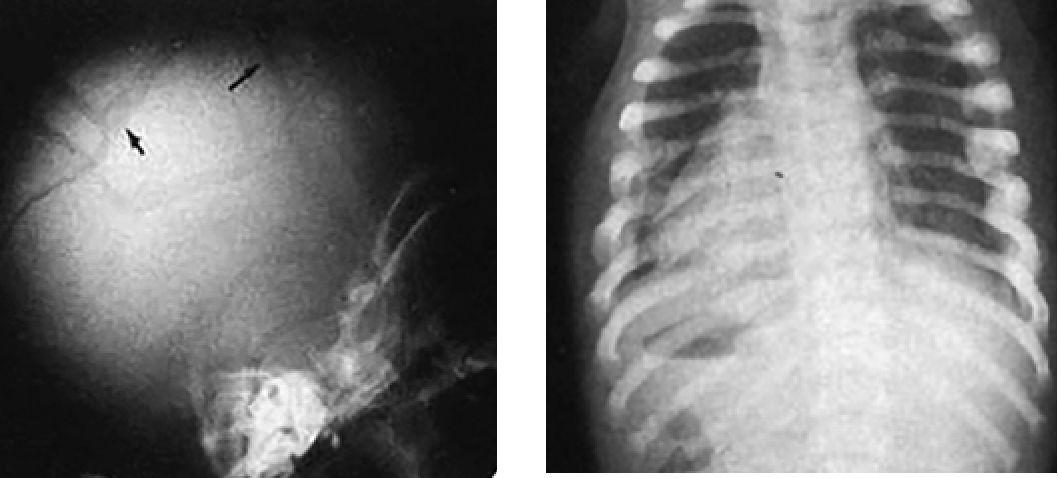

Наиболее частые варианты переломов вследствие жестокого обращения - переломы ребер, метафиза костей в результате тряски за конечность, акромиального отростка лопатки, грудины, стоп, остистых отростков и тел позвонков, множественные переломы черепа (рис. 2).

Рис. 2. Множественные переломы вследствие жестокого обращения с детьми

Подозревать травму головы вследствие жестокого обращения следует при наличии других повреждений (гематомы, переломы), кровоизлияний в сетчатку глаза (отмечают в 70-80% случаев синдрома тряски ребенка). Синдром травматической тряски младенца (Shaken baby syndrome) следует подозревать у всех детей раннего возраста с любыми внутричерепными повреждениями, кровоизлияниями в сетчатку глаза, при несопоставимости тяжести состояния и данных анамнеза. Часто родители детей, обратившихся за медицинской помощью, в качестве причины внутричерепной травмы называют падение ребенка с кровати.